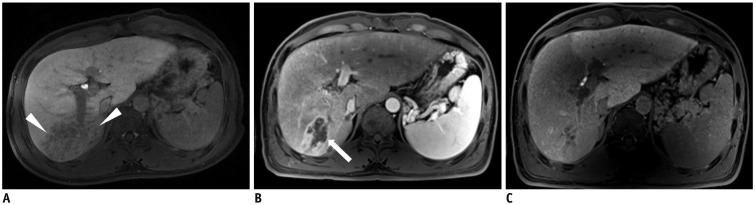

Radioembolization using beta-emitting yttrium-90 microspheres is being increasingly used for the treatment of primary and metastatic liver cancers. It is a form of intra-arterial brachytherapy which delivers intense radiation to liver tumors with little embolic effect; this mode of action results in unique post-treatment imaging findings. It is important to understand these imaging findings to avoid misinterpretation of tumor response and to determine further management of the disease. Herein, we discuss the current concepts for assessing tumor response, common post-treatment imaging features, and associated complications following radioembolization.

放射性栓塞术使用β发射的钇-90 微球,越来越多地用于治疗原发性和转移性肝癌。这是一种动脉内近距离放射治疗,对肝脏肿瘤有强烈的辐射作用,栓塞作用很小;这种作用模式导致了独特的治疗后影像学表现。了解这些影像学表现非常重要,以避免对肿瘤反应的错误解读,并确定疾病的进一步治疗。在此,我们讨论评估肿瘤反应的当前概念、常见的治疗后影像学特征以及放射性栓塞后的相关并发症。